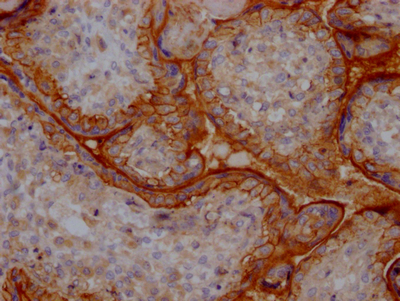

IHC image of CSB-RA279866A0HU diluted at 1:100 and staining in paraffin-embedded human placenta tissue performed on a Leica BondTM system. After dewaxing and hydration, antigen retrieval was mediated by high pressure in a citrate buffer (pH 6.0). Section was blocked with 10% normal goat serum 30min at RT. Then primary antibody (1% BSA) was incubated at 4℃ overnight. The primary is detected by a Goat anti-rabbit IgG polymer labeled by HRP and visualized using 0.05% DAB.